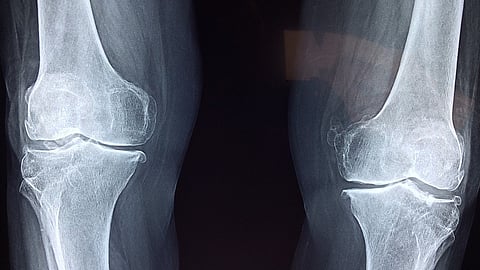

A recent study published in Osteoporosis International revealed a disturbing trend: men are more likely than women to sustain fractures from falls. The study, titled "A meta-analysis of previous falls and subsequent fracture risk in cohort studies," examined data from 46 prospective cohorts encompassing more than 900,000 people, providing critical insights into fracture risk assessment and prevention techniques.

It was discovered that those who had experienced falls in the previous year were considerably more likely to sustain any kind of clinical fracture, major osteoporotic fracture, or osteoporotic fracture. or hip fracture. Moreover, one or more previous falls were associated with an increased risk of death among both women and men.

Interestingly, bone mineral density had little bearing on the elevated fracture risk associated with prior falls, highlighting the independent importance of falls as a risk factor. This suggests that a previous fall in the past year confers a significantly increased risk of various types of fractures, regardless of bone density.